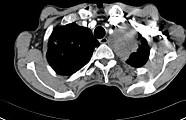

问题 56岁,男,意识错乱情绪不稳定1周,请结合胸片和CT图,选出最可能的诊断 ( )

选项 A.肺癌 B.错构瘤 C.胸内甲状腺肿 D.韦格肉芽肿 E.胸腺瘤

答案 A